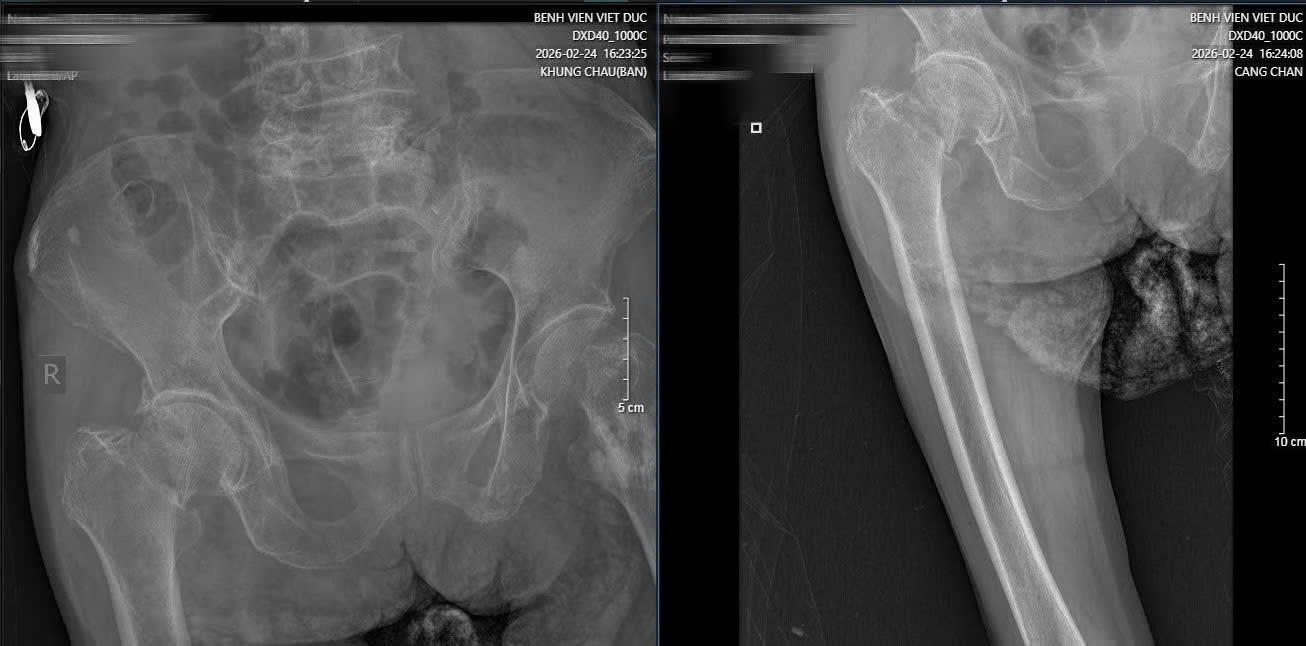

Hình ảnh phim X-quang cụ bà 89 tuổi nhập viện gãy cổ xương đùi phải và hình ảnh chụp CT ổ bụng và phát hiện khối u ruột non gây lồng ruột.